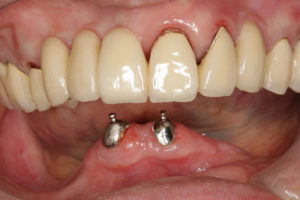

普通、インプラントを入れたら骨に結合するまで3〜6ヶ月待ってからでないと負荷をかけられないのですが、4本以上のインプラントを確実に固定させ、それを仮歯でしっかりと連結することで、骨との結合を待つことなく負荷をかけることが可能となります。

ですから、手術前は入れ歯だったのが、手術後にはまるで自分の歯のようなブリッジが出来上がり、食事ができるようになります。手術方法によってはほとんど腫れや痛みもありません。(今回は、余分な骨を削ったり、骨移植を行ったりしたため、翌日若干の痛みが出たそうです。)

手術当日に入れたブリッジは仮の歯なので、硬い物は控えて頂いていますが、3ヶ月後には最終的な物が出来上がり、なんでも食べられるようになります。入れ歯では食べられないような、アワビやタコのようなものも食べられるようになります。